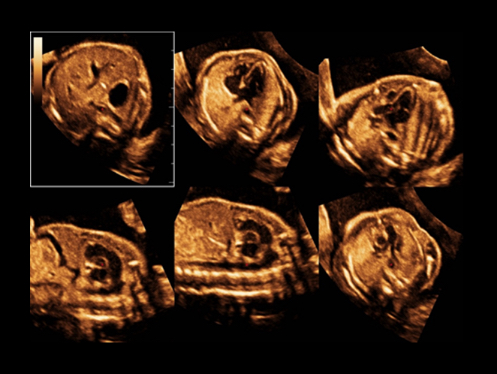

ImĂĄgenes clĂnicas